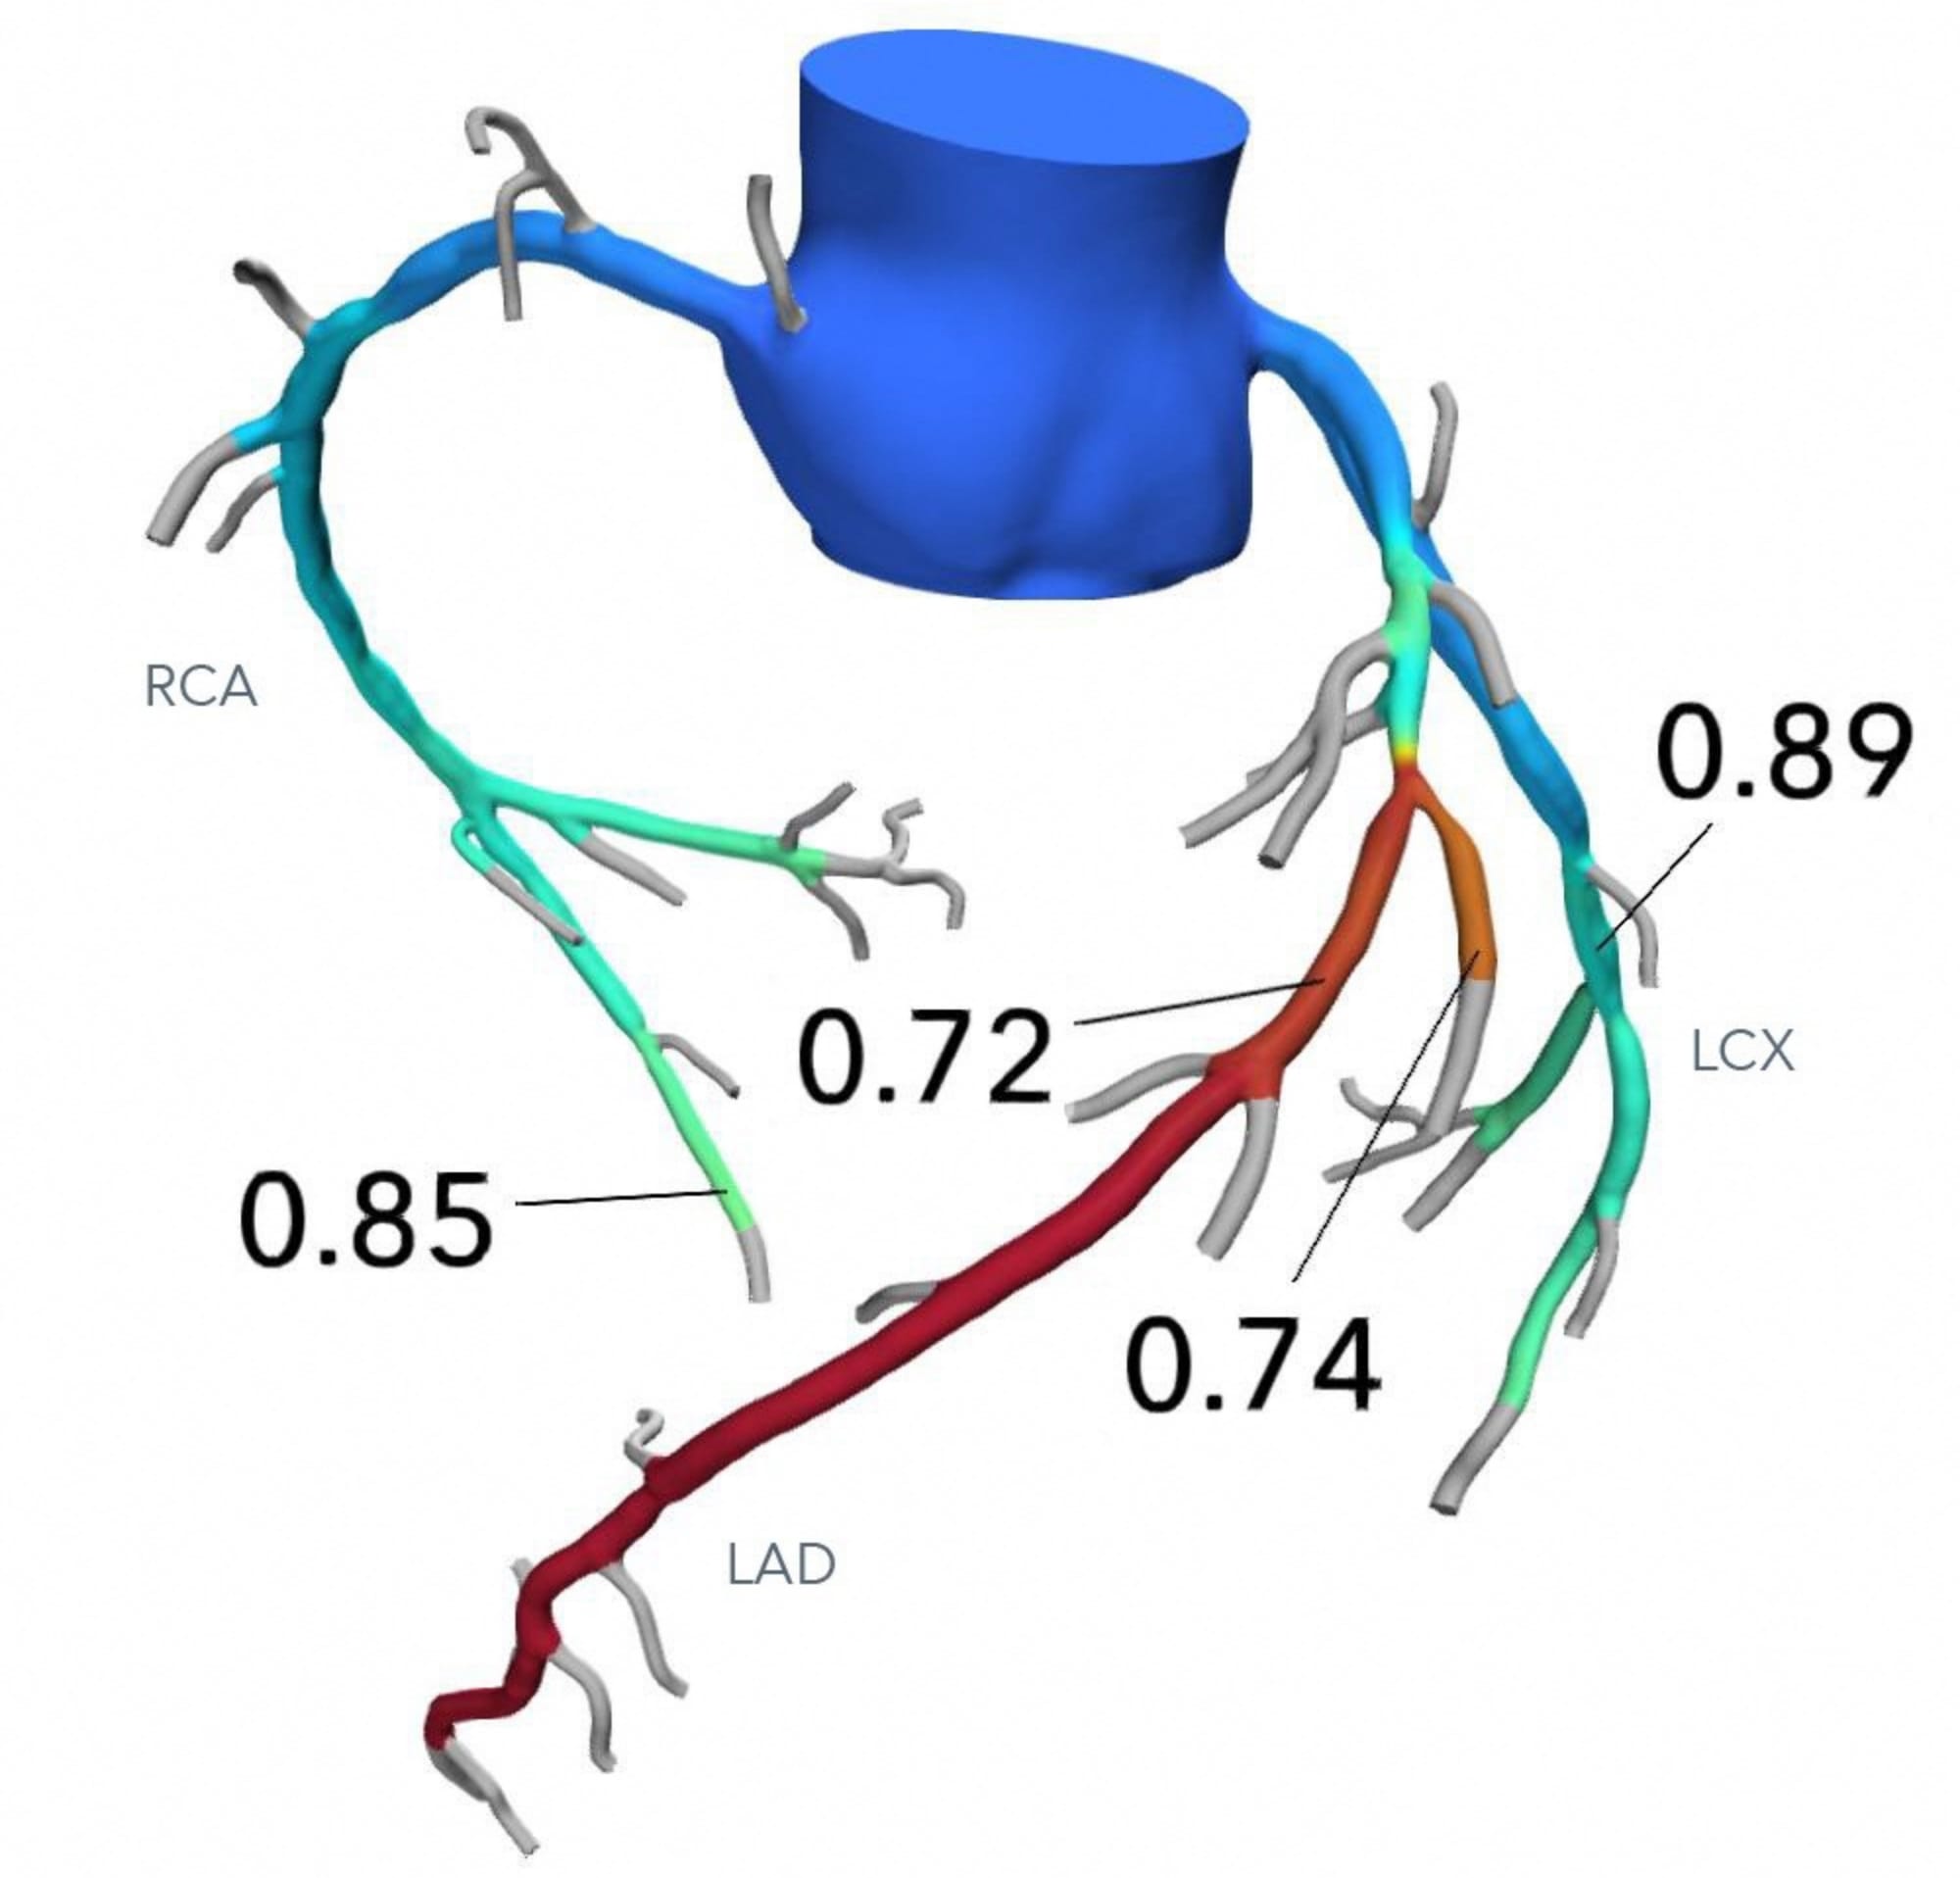

狭心症|横浜市の総合病院 横浜市立市民病院, 冠動脈疾患における CT-SPECT Fusion Imagingの有用性―ziosoft,